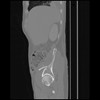

7 CUERPO,CE,Sagittal,3.000,CUERPO,Sagittal,